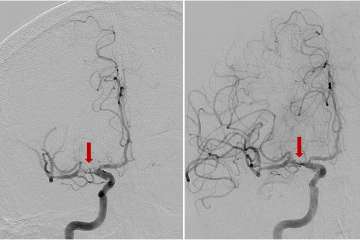

Anterior-Posterior view of a right frontal lobe AVM (red arrow) prior to surgery (left) and after embolization and surgical complete removal and cure (right).